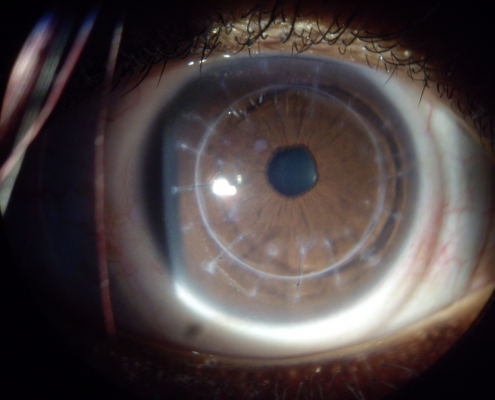

O ceratocone é uma doença progressiva e não inflamatória da córnea. Sua principal característica é o afinamento gradual e a deformação dessa estrutura, o que leva à sua curvatura irregular, dificultando a passagem correta da luz até a retina. A condição costuma surgir na adolescência ou no início da vida adulta e pode evoluir de forma variável.

- Biomicroscopia: permite observar sinais clínicos do ceratocone em lâmpada de fenda.